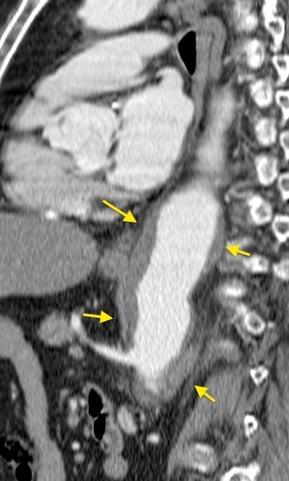

“Draped aorta”.

Indica rotura aórtica reciente. Se manifiesta por una pared aórtica posterior o el contacto con el borde lateral vertebral borrados por la hemorragia.

Rotura aneurisma de Aorta descendente.

Dolor. (10 días antes: "Rotura inminente”)